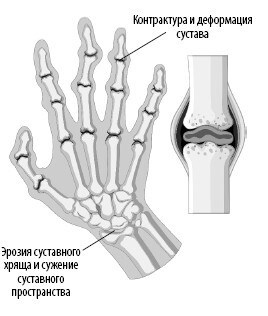

Здоровые рука и суставы. ![]() Рука с артритными суставами. Кроме того, старение приводит к дефициту проприоцептивных навыков – ощущения положения тела и ориентации в пространстве. Он возникает при снижении количества тензорецепторов в связках, из-за чего нарушается восприятие расположения суставов в пространстве. ![]() Старение суставного хряща приводит к воспалению и аномальному росту. Стареющие мышцы Саркопения – это термин, под которым подразумевают снижение массы скелетных мышц и их возможностей нормального функционирования. Этот прогрессирующий возрастной синдром сопряжен и с другими недостатками: снижением качества жизни и повышенным риском инвалидности и смерти. К потере мышечной массы приводит истончение миофибрилл внутри мышечных волокон, из-за чего снижается толщина самого волокна (чаще встречается у волокон 2-го, быстро сокращающегося типа). Миофибриллы атрофируются со скоростью от 3 % до 8 % в каждые 10 лет (в возрасте от 30 лет). А для людей старше 65 лет этот показатель еще больше возрастает. Потеря мышечной массы может быть связана c уменьшением количества самих волокон. В возрасте от 24 до 50 лет скорость атрофии мышечных волокон увеличивается с 5 % до 35 %. Считается, что возрастные изменения в нервно-мышечном соединении приводят к тому, что связанный с ним нейрон отделяется от мышечного волокна (лишается иннервации), а затем умирает в результате апоптоза (см. параграф «Запрограммированная гибель клетки: апоптоз» на стр. 51). ![]() На этих МРТ-снимках изображены бедра здорового 31-летнего мужчины (вверху) и здорового 81-летнего мужчины (внизу). Потеря мышечной массы и увеличение фиброзно-жировой ткани – характерные признаки саркопении. Процесс старения не щадит и сателлитные клетки, которые в норме отвечают за восстановление поврежденных мышц. С возрастом их популяция сокращается на целых 50 %. ![]() Считается, что танцы – это увлекательный способ замедлить или обратить вспять процесс потери скелетных мышц. Кроме того, у пожилых людей танцы улучшают здоровье мозга. На работоспособность мышц влияет и тип разрушенных мышечных волокон. Оказывается, что старение приводит к потере двигательных нейронов, которые иннервируют 2-й тип мышечных волокон, быстро сокращающихся. Такое изменение не только уменьшает количество волокон, но и способствует тому, что некоторые волокна начинает иннервировать 2-й, медленно сокращающийся тип двигательных нейронов. Это, в свою очередь, изменяет скорость реакции, удельную мощность мышц, их координацию и силу. Мышечная архитектура страдает и из-за разрастания фиброзно-жировой ткани. Все это накладывается на сопутствующие возрастные изменения и влияет на динамику мышечно-костных отношений. В результате снижается действенность упражнений, направленных на увеличение мышечной силы и костной массы. Многие исследователи говорят, что скорость потери мышечной массы можно компенсировать регулярными упражнениями (особенно танцами), поэтому пословица «движение – жизнь» глаголет истину. |